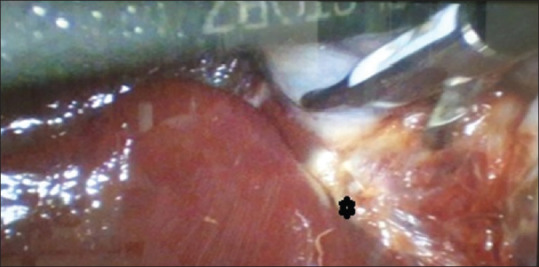

图 11

胆囊体部粘连致密的术中视图。(包含图片、插图等的外部文件。